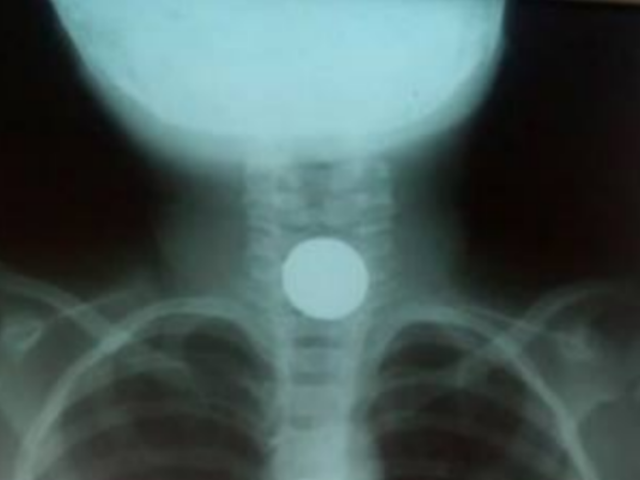

En un descuido, una menor de apenas cuatro años cogió una moneda de cincuenta céntimos y la ingirió, quedando atascada en la parte de su faringe. Ahora, ella se encuentra en estado crítico a la espera de las atenciones médicas en el estado ‘Santa Gema’ en Yurimaguas.